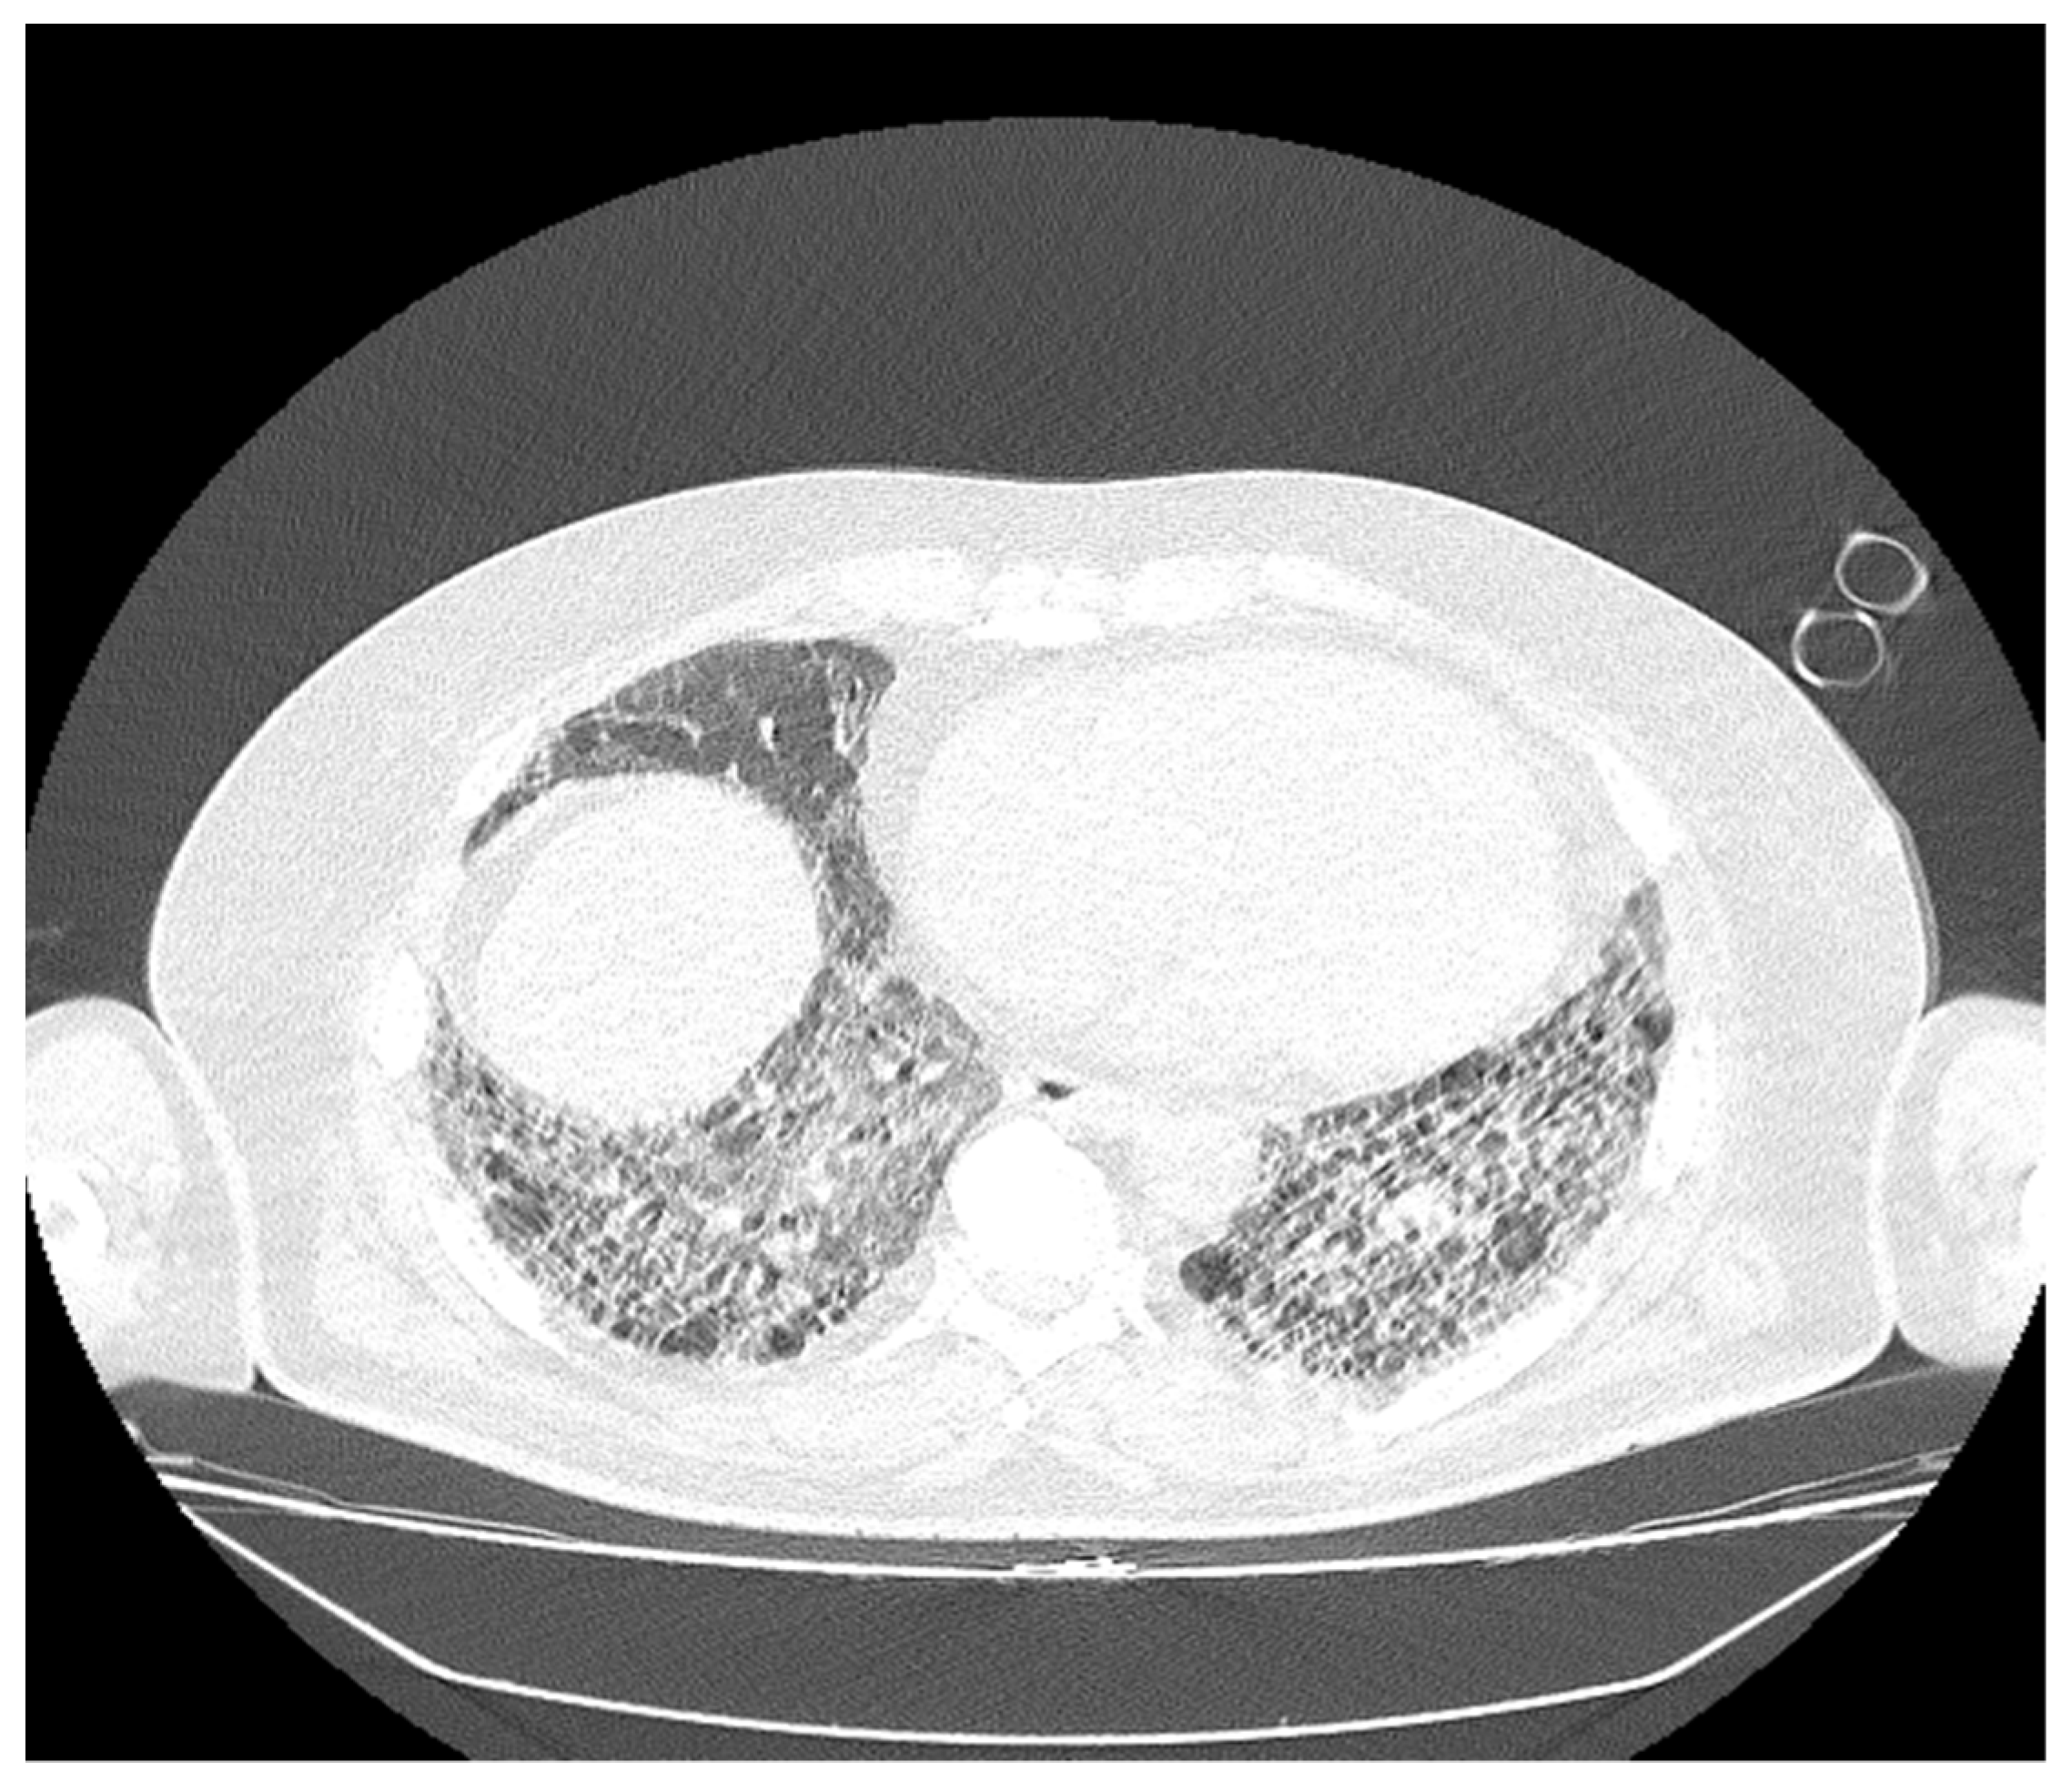

Figure 4. The bilateral pulmonary bases presented dispersed reticulonodular opacities, which associate with traction bronchiectasis: an imaging aspect that illustrates end-stage pulmonary fibrosis (UIP pattern). The association of extensive ground-glass opacities is associated with the extensive inflammatory process (NSIP pattern).